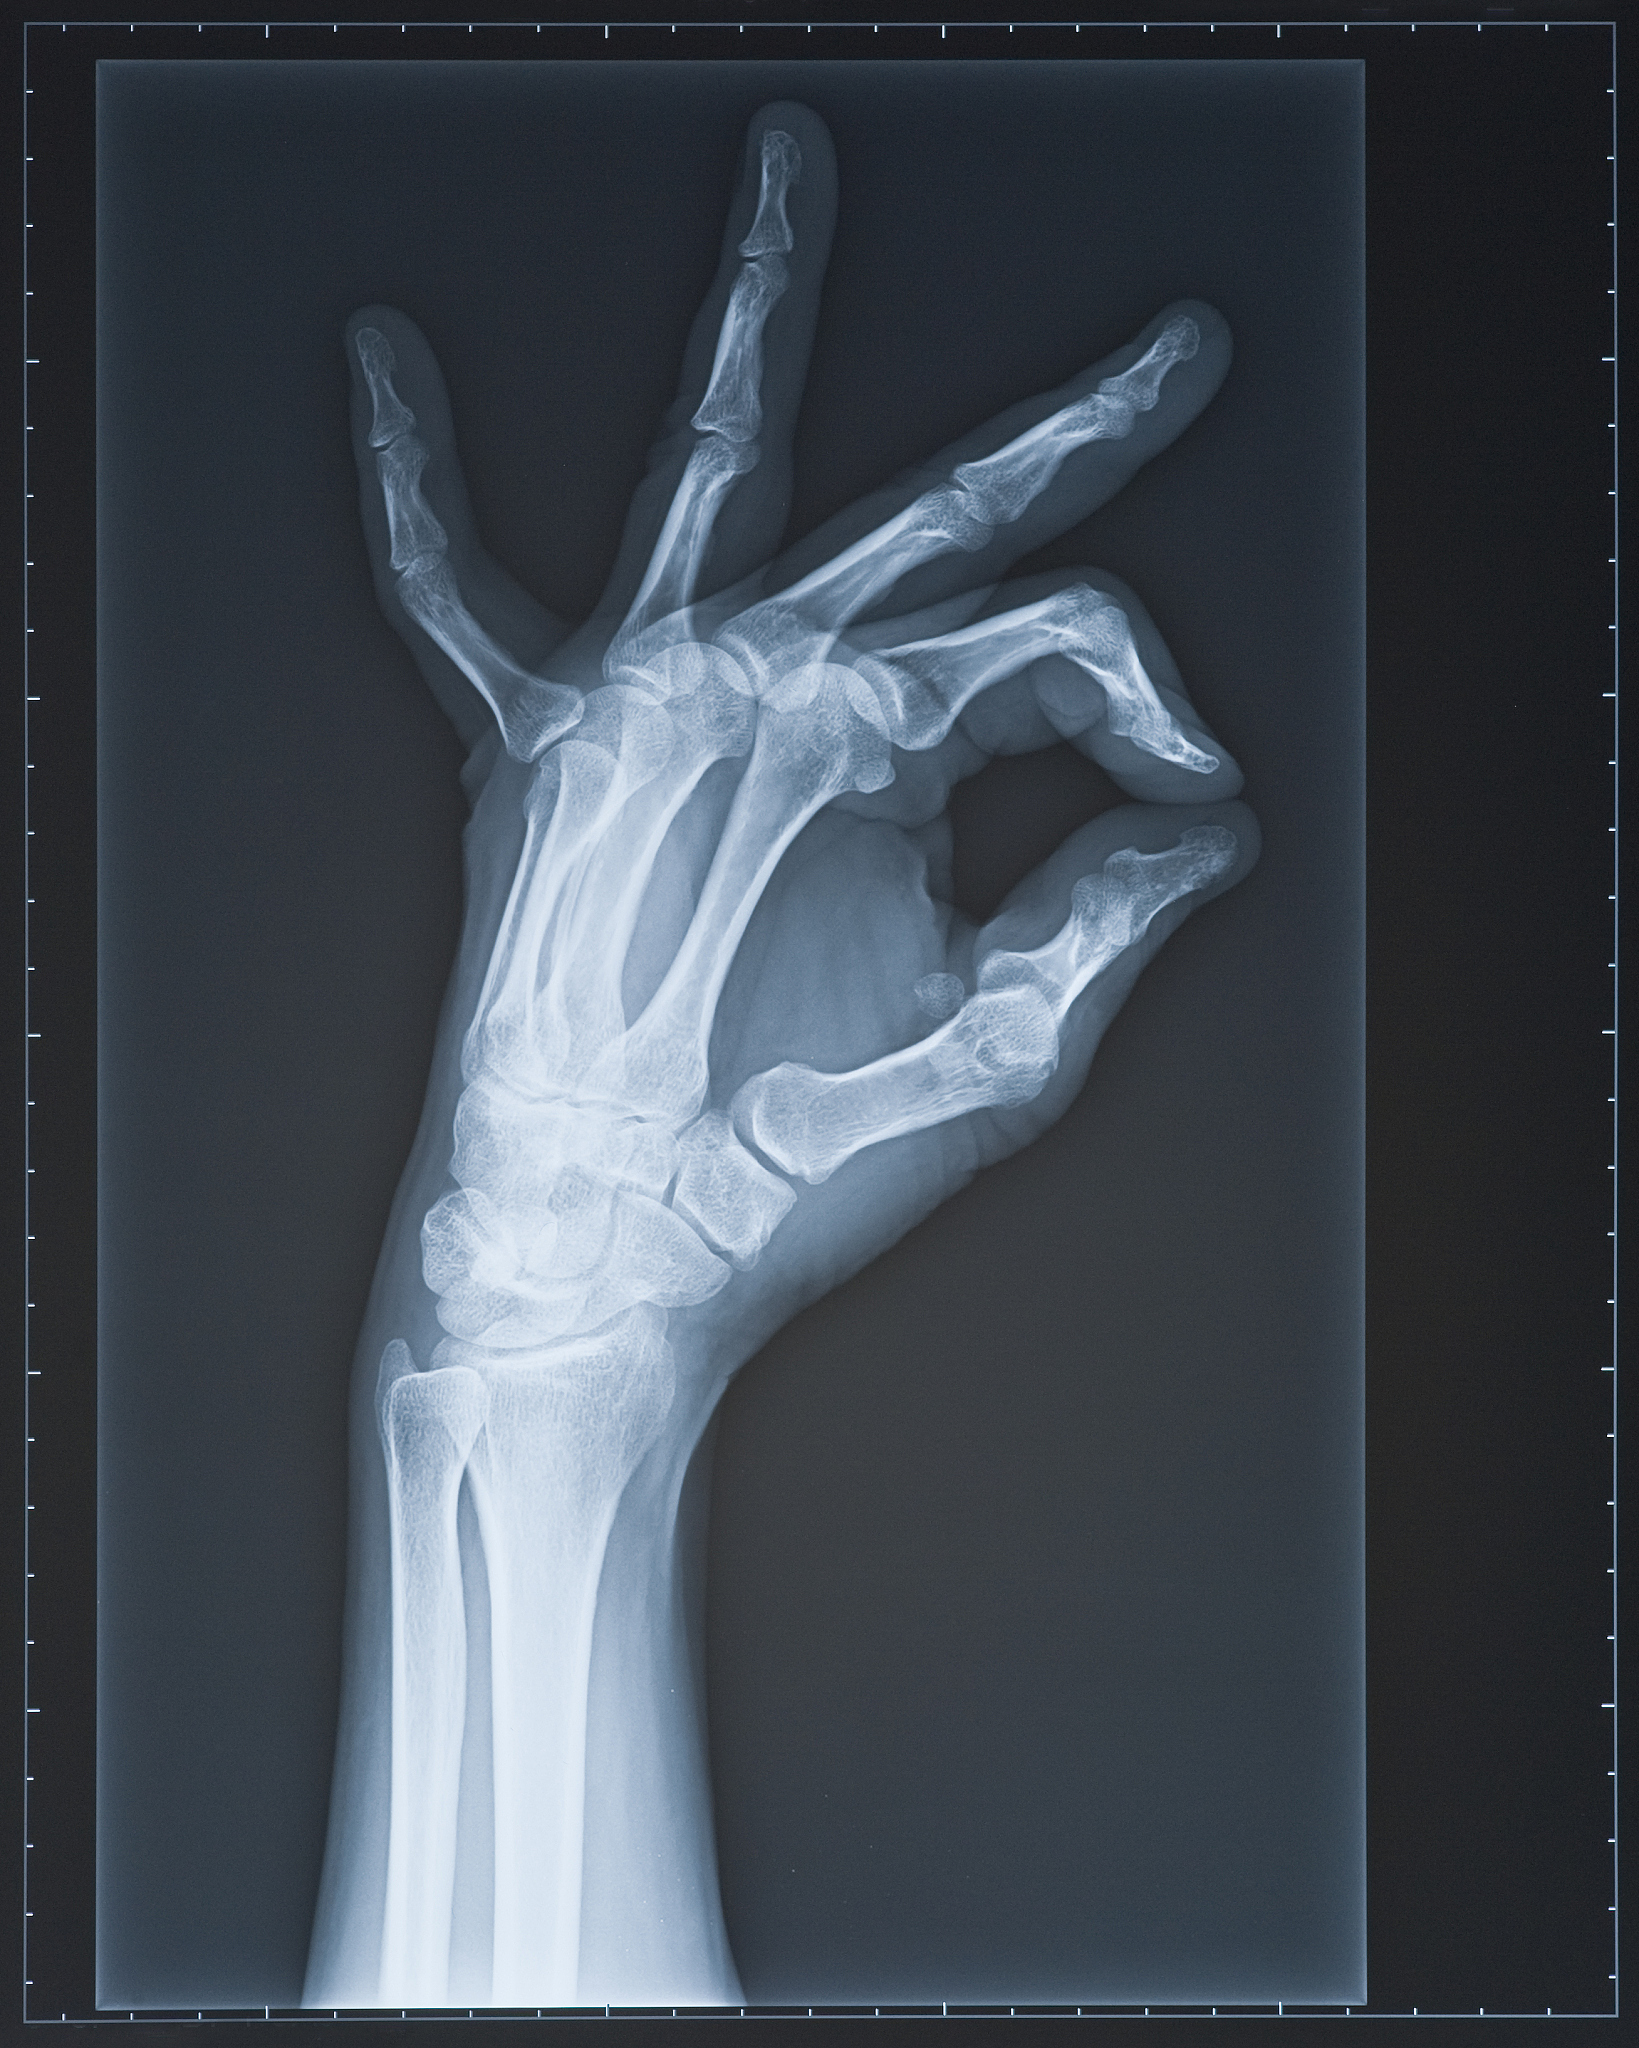

尺骨和桡骨之间并非简单连接,而是形成了一个复杂的关节系统,被称为桡尺关节。正是这个关节赋予了前臂在垂直轴上进行旋转运动的能力。

• 内旋:手掌转向内侧的运动。此时,尺骨充当旋转轴心,桡骨则围绕着尺骨进行旋转,带动前臂内侧发生运动。 - 外旋:手掌转向外侧的运动。与内旋相反,外旋时桡骨成为轴心,尺骨围绕桡骨旋转,进而带动前臂外侧发生运动。